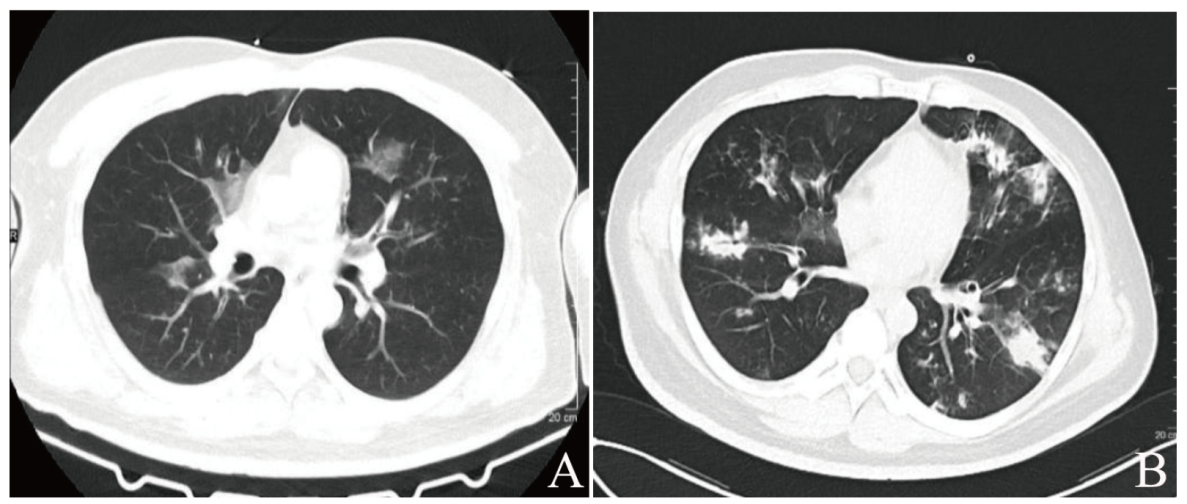

实验室及辅助检查:尿常规示酮体(++++),葡萄糖(++++)。随机静脉血糖17.16 mmol/L。动脉血气分析示酸碱度7.047,氧分压66.8 mmHg,二氧化碳分压23.4 mmHg,阴离子间隙24.4 mmol/L,碳酸氢根离子6.4 mmol/L。血常规示血红蛋白164 g/L,红细胞5.65×1012/L,白细胞16.87×109/L,中性粒细胞绝对值14.63×109/L,淋巴细胞绝对值0.74×109/L,血小板233×109/L。血液生化示肝肾功能无异常。血钾4.96 mmol/L、钠133 mmol/L、镁0.96 mmol/L、磷1.19 mmol/L(参考值范围0.8~1.5 mmol/L)、钙2.21 mmol/L。GHbA1c 12.7%。甲状腺功能提示低T3综合征。肿瘤标志物、肥达外斐反应、风湿免疫相关检查均无异常。心电图示窦性心动过速。头颅CT未见异常。肺部CT示双肺散在渗出,见图1A。肺动脉造影CT血管成像未见明显栓塞。腹部CT示胰腺萎缩、胰头部点状钙化,胆囊多发结石、慢性胆囊炎。痰涂片仅检出少量革兰阳性球菌,2次痰培养、3次血培养、中段尿培养、乙型流感病毒RNA、疟原虫等均阴性,腹部B超提示脂肪肝及胆囊结石。初步诊断:①DKA;②肺部感染。

图1 一例DKA合并低磷血症、烟曲霉菌肺炎患者的CT检查图

注:A为2022年3月18日肺部CT表现;B为2022年3月28日复查肺部CT表现。

入院第8日查真菌D-葡聚糖530.2 pg/mL(参考值范围0~100.5 pg/mL)。停用莫西沙星,改予伊曲康唑胶囊0.1 g、2次/日。并停用胰岛素皮下泵,改予德谷胰岛素35 U+赖脯胰岛素注射液(优泌乐,早15 U、中15U、晚11 U)控制血糖。经治疗后患者仍偶有发热,最高38.3℃,脉搏波动于92~119次/分,呼吸波动于16~22次/分,面罩吸氧时血氧饱和度波动于92%~96%,不吸氧时为86%。血糖波动于14~21.4 mmol/L,空腹血糖16.5 mmol/L。入院第10日复查肺部CT提示病灶增多,见图1B。遂进一步完善电子气管镜检查,取肺泡灌洗液送院外机构实验室行定量宏基因组检测,检出烟曲霉菌,明确诊断为烟曲霉菌肺炎。因本院内无针剂,故于入院第18日调整伊曲康唑胶囊用量为0.2 g、2次/日,治疗6 d后患者病情明显好转,无需吸氧,日常活动无不适,胸闷缓解,体温36.5℃、脉搏78次/分、呼吸20次/分。胰岛素用量改为德谷胰岛素 20 U+ 优泌乐(早10 U、中3 U、晚3 U),血糖波动于4.3~14.6 mmol/L,空腹血糖5.4 mmol/L。结合患者病情及糖尿病自身抗体阴性,考虑为2型糖尿病。